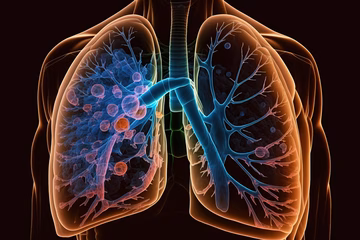

Uspjeh hrvatskih i kanadskih znanstvenika: Tri potencijalna lijeka za rak pluća Znanost | 25. velj. | 0